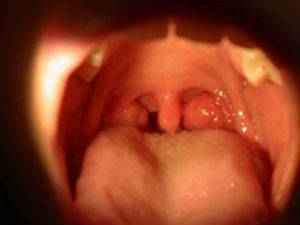

Коротко об аденоидахАденоидами называется патологически увеличенная носоглоточная миндалина...